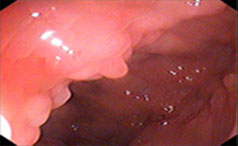

胃息肉的存在会干扰胃的正常消化功能,从而导致消化不良症状的出现。此外,胃息肉如果增大或破裂,会刺激胃壁,引起疼痛和呕血等症状。胃息肉也可能破......【详情】

常见症状:上腹隐痛、腹胀、不适

无痛性便血、脱垂

【导语】胃肠息肉的发生与多种因素有关,应该定期进行胃肠镜检查,以便及......【详情】